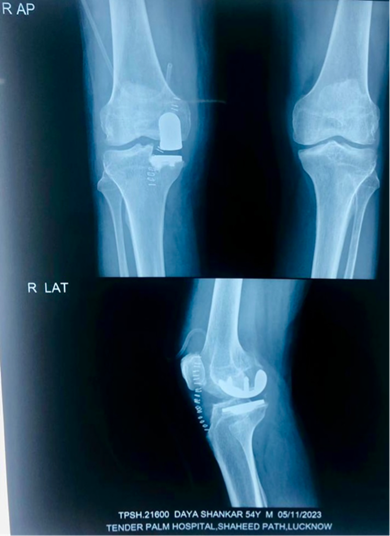

I specialised in all kinds of Knee and Shoulder surgery be it Joint Replacements or Joint Preservation, be it conventional technique Arthroscopic or Robotic

Knee Replacement Surgery, also known as knee arthroplasty, is a surgical procedure that aims to relieve pain and restore function in severely damaged knee joints. It involves replacing the damaged joint surfaces with artificial implants made of metal and plastic.